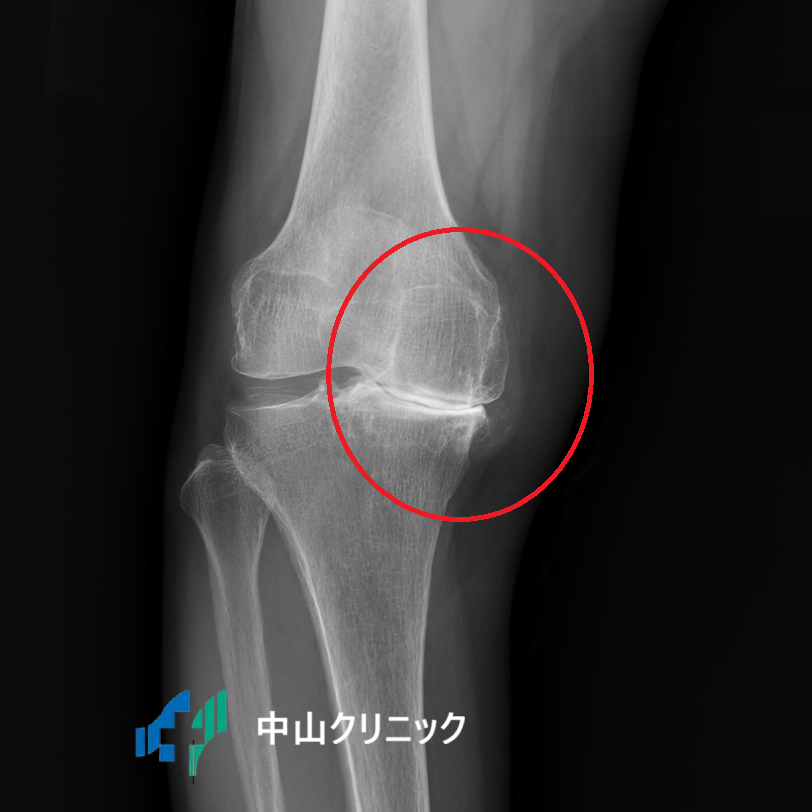

⑤ 半月板や靭帯の損傷 🤕

膝内側の骨髄浮腫 |

内側半月板後根損傷 |

膝の安定性を保つために重要な役割を果たしているのが、C型をした軟骨組織「半月板」と、骨と骨をつなぐ強靭な「靭帯」です。

スポーツや転倒などで膝をひねると、これらの組織が損傷し、「膝の裏が痛い」と感じることがあります。

特に、半月板の後ろ側(後根)が断裂すると、「ブチッ」という音とともに激痛が走り、急激に膝の状態が悪化することがあります。

これを見逃すと、骨が壊死(えし)してしまい、歩行が困難になるほどの痛みに発展する可能性も。

とても怖い損傷です。

また、バイクや自転車での転倒、スポーツ中の転倒などで膝を曲げたまま強い衝撃を受けると、膝の安定を司る「後十字靭帯」が断裂し、膝の裏に強い痛みが出ます[3]。

⑥ 実は見落とされがちな骨折 🦴

「骨折したら歩けないでしょ?」と思うかもしれませんが、実はそうとも限りません。

大きな骨折はすぐにわかりますが、小さな骨折、特に後十字靭帯が付着している部分が剥がれる「裂離骨折(れつりこっせつ)」は、レントゲンでも見落とされることがあるのです。

膝を曲げたまま転倒した際に起こりやすく、歩いてクリニックに来られる方も少なくありません。